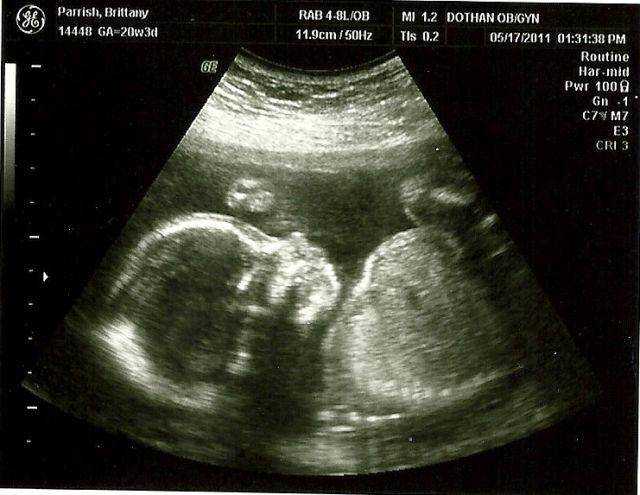

Если УЗИ проводится на 29 неделе беременности, четко видна половая принадлежность малыша. У мальчиков на этом сроке продолжается опускание яичек в мошонку. У девочек клитор немного выдается, так как он еще не прикрыт малыми половыми губами.

В период развития беременности 29 недель наступает время, когда у малыша можно услышать биение сердечка. Также можно тщательно рассмотреть и прослушать работу внутренних органов ребенка, на этом сроке он уже достаточно крупный для этого. Вес малыша на двадцать девятой неделе беременности должен составлять не менее 1200 граммов, а длина тела может превышать 35 сантиметров.

Сейчас плод растет более интенсивно и также набирает вес. Его рост около 38 см, а вес доходит до 1,3 кг. Ваш малыш размером с пекинскую капусту.

Щечки постепенно округляются вместе с другими частями тела. Так как половые органы сформировались достаточно хорошо, на УЗИ можно уже безошибочно определить пол малыша. С каждым днем организм ребенка начинает функционировать все лучше, превращаясь в гармоничную отлаженную систему. Связки и мышцы продолжают совершенствоваться и крепчать, что ощущается по силе толчков. Учитывая то, что места для кувырканий становится намного меньше, каждый переворот с головы на ноги и наоборот будет четко ощущаться мамочкой.